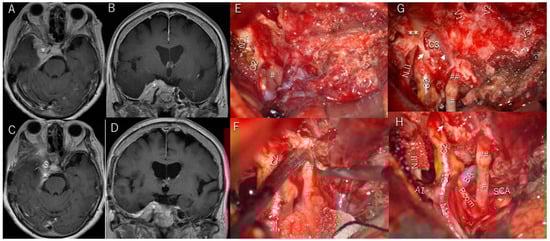

3.6. Illustrative Patient Cases

| 1 | y | y | entire lateral wall of cavernous sinus | Totally with sacrifice of all cranial nerves | 4 | y/no change | y/sacrifice | y/sacrifice | brain stem swelling/complete recovery | |